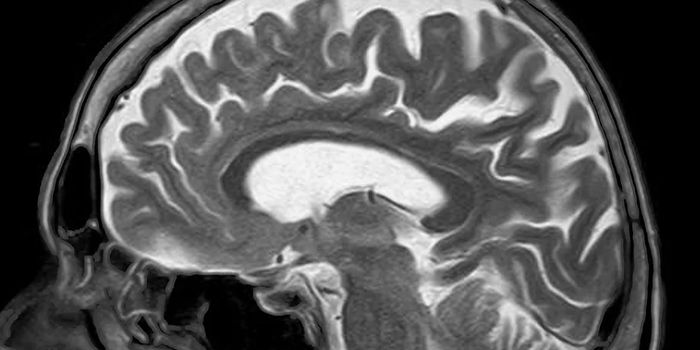

FEB 17, 2025NeuroscienceResearchers have discovered a new type of neuron that plays a critical role in recognition memory.